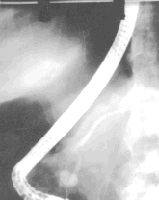

Figura 1.

Quiste del colédoco tipo I, con dilatación uniforme del colédoco, (Radiografía en posición PA).